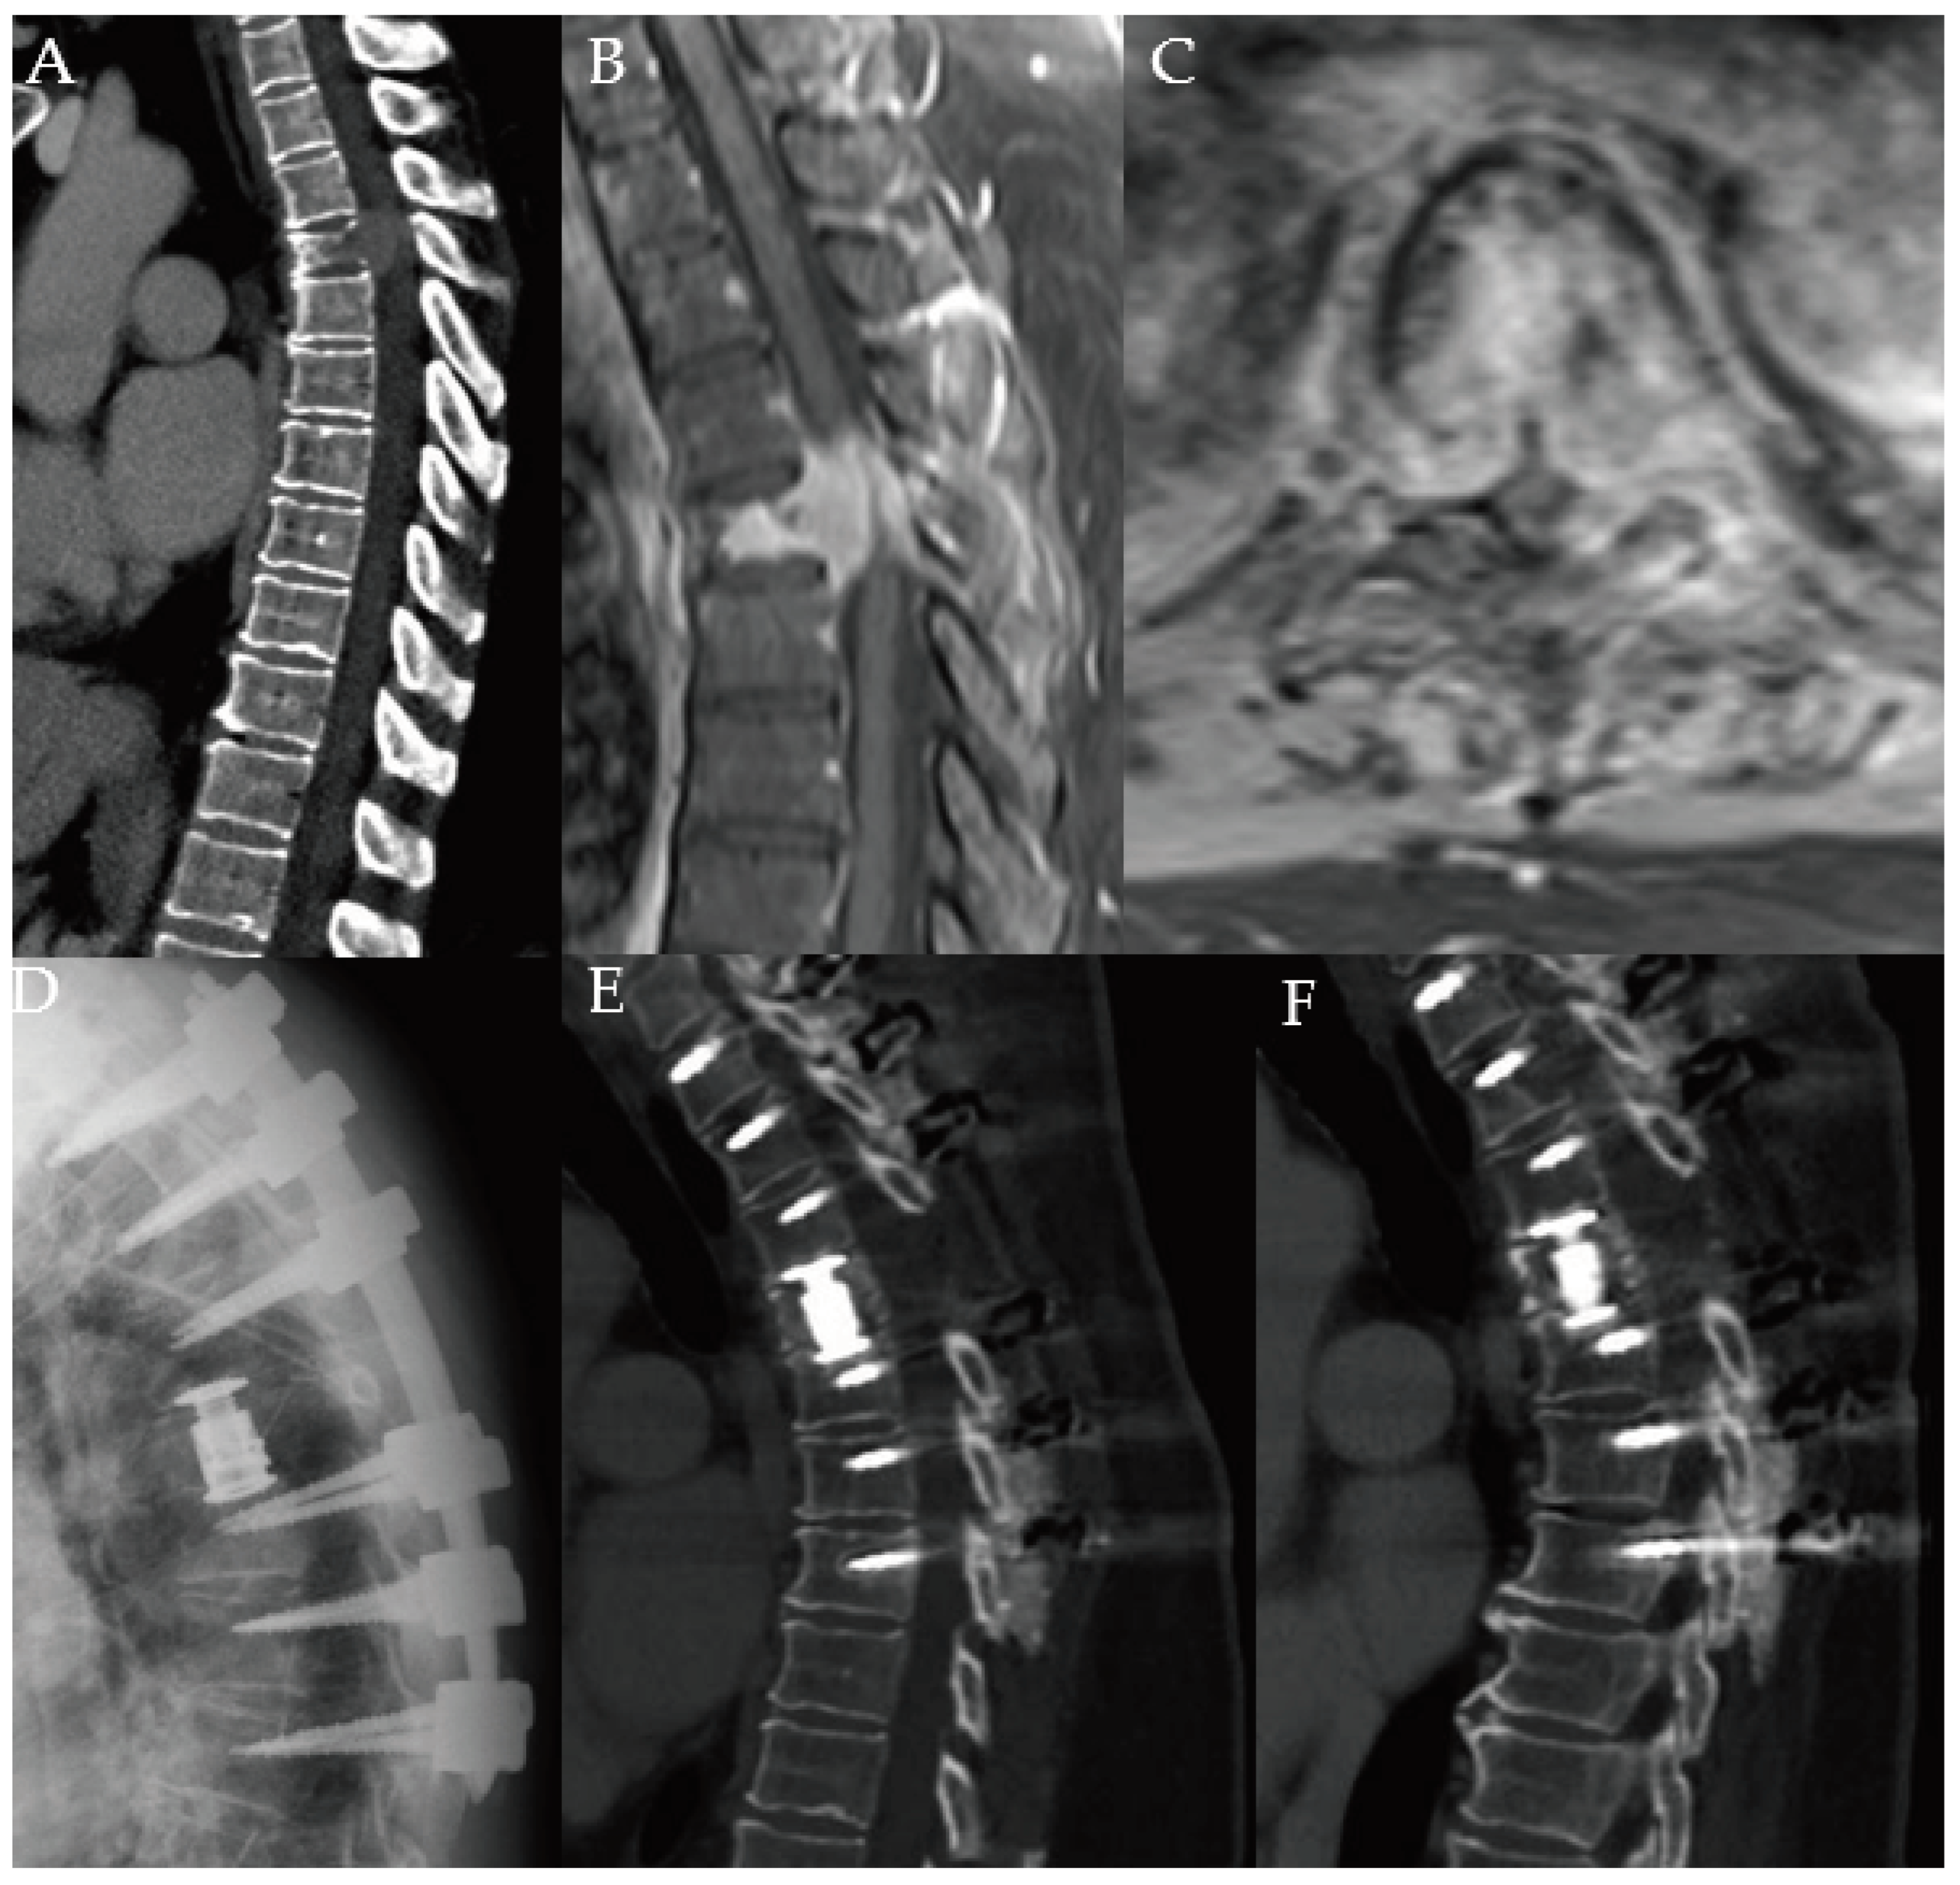

Preprints 97859 g001

Figure 2. A 66-year-old female with a history of metastatic breast cancer. She developed low back and right leg pain and underwent vertebroplasty as depicted on plain anteroposterior (A) and lateral (B) radiographs. Eight months later, she began feeling pain and weakness in the right leg requiring significant opioid pain medication usage. Patient underwent L3 corpectomy through a lateral approach with carbon fiber prosthesis and posterior instrumentation spanning T12-L5. Postoperative T2-weighted MRI in the lateral (C) and axial (D) views show decompression of the canal, and restoration of height and spinal alignment. Anteroposterior (E) and lateral (F) plain radiographs obtained one year after surgery show alignment and height maintained without kyphosis. She was ambulatory with a cane and was very pleased with her outcome. She survived over 2.5 years after her surgery.

Given the continued advances in cancer survivorship, this treatment paradigm may need to be revisited. While preserving and restoring neurological function remains a primary goal of spinal oncology surgery, maximal tumor debulking with excision of part or all of the vertebral body (corpectomy) for improved local disease control, restoration of spinal alignment and spinal stabilization with the goal of long-term pain relief, functional independence, and improved disease-free survival may need to be taken into account in a select cohort of patients [9,18,19]. Corpectomy of one or more levels may prove indicated and necessary where other less invasive treatment modalities fail leading to gradually worsening clinical outcome (Figure 2). In oligometastatic spinal disease (< 5 sites of metastases, patients with good functional status and favorable long-term prognosis, this approach would target long-term spinal stabilization, reduce the risk of local tumor recurrence, and reduce the need for further surgical intervention. However, the evidence concerning this matter is still pending [12].